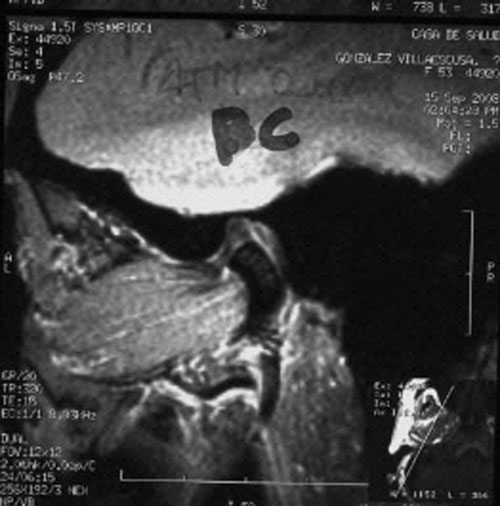

RMN de ATMs (17-09-2008): Dentro de la normalidad.

– ATMs dentro de la normalidad.

PRUEBAS DIAGNOSTICAS COMPLEMENTARIAS:

REF. 3A